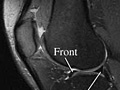

doctor in 1 to 2 days. Magnetic resonance imaging (MRI) of the knee Normal: | The

ligaments,

meniscus,

tendons, bones, and joints look normal in size, shape,

and location. |

---|

No growths, such as tumors, are

present. | No broken bones (fractures),

extra fluid, or loose bodies are present. | No signs of inflammation or infection in

bones, joints, or soft tissues are present. | Abnormal: | Bones show an injury or a fracture. The MRI

also may show a collection of fluid, which could mean an infection is

present. |

Ligament or meniscus tears are

present. | Tendon tears are present. The MRI may also show a thickening, meaning surgery or a tear you had in the past or repeated stress. | Growths, such as tumors, are

present. | Changes common to

arthritis are present. | What Affects the TestReasons you may not be able to